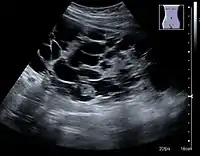

The hydronephrosis is typically graded visually and can be divided into five categories going from a slight expansion of the renal pelvis to end-stage hydronephrosis with cortical thinning (Figure 15). The evaluation of hydronephrosis can also include measures of calyces at the level of the neck in the longitudinal scan plane, of the dilated renal pelvis in the transverse scan plane and the cortical thickness, as explained previously (Figure 16 and Figure 17).[1]

Figure 15. End-stage hydronephrosis with cortical thinning. Measurement of pelvic dilatation on the US image is illustrated by ‘+’ and a dashed line.[1]